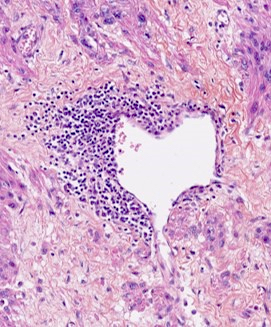

Microscopic (histologic) description

- Conventional / usual leiomyoma (spindle):

- Well defined borders

- Normocellular

- Intersecting fascicles of monotonous spindle cells with indistinct borders, eosinophilic cytoplasm, cigar shaped nuclei (with tapered ends) and small nucleoli

- Atypia: absent or mild

- Mitoses: rare (in general < 5/10 high power fields)

- Blood vessels with thick walls

- With or without infarct type necrosis, hyalinization, calcification, cystic change

Microscopic (histologic) images

Contributed by Sabrina Croce, M.D., Ph.D., Kristina Doytcheva, M.D., Jennifer A. Bennett, M.D. (Case #508) and @Andrew_Fltv on Twitter